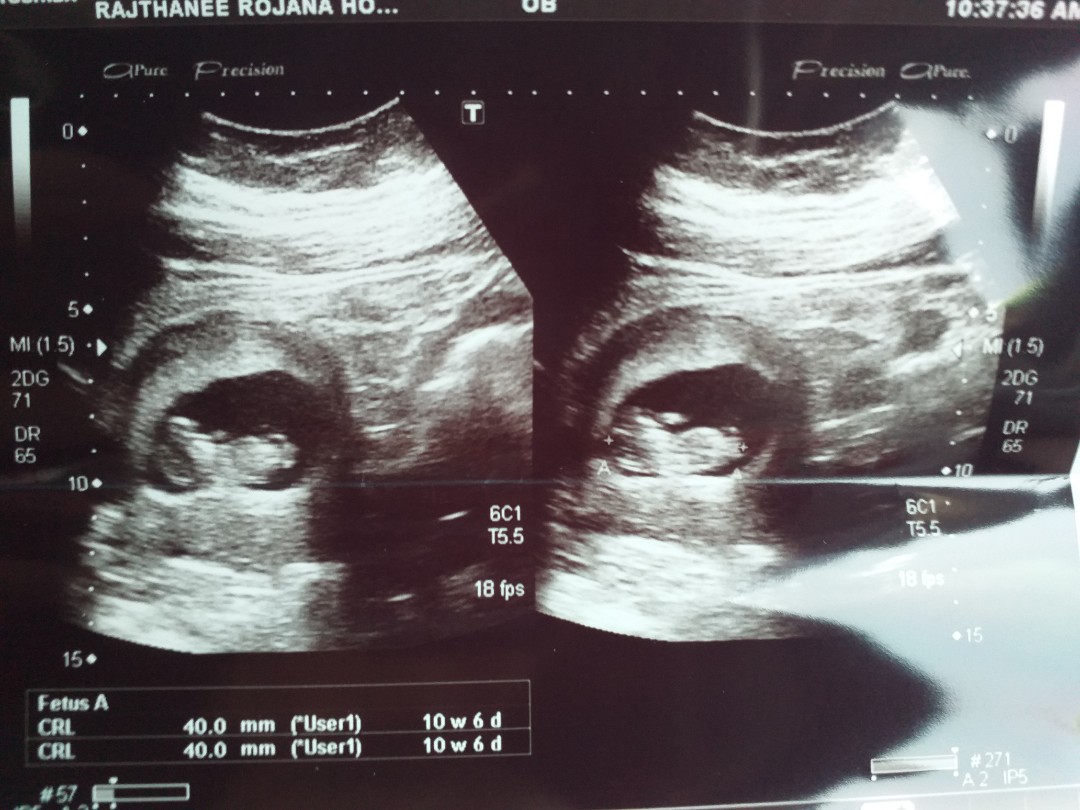

3 ธันวา ซาวด์ตอน9วีคค่ะ

3 ธันวา ค่าา ซาวส์ตอน 9w